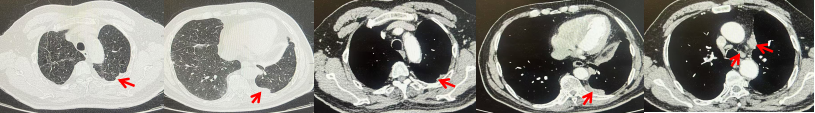

2024.11.19患者出现右侧胸痛,复查胸部CT检查示右侧胸膜肿物,大小约31mmX24mm,右侧4、5肋骨骨质破坏,考虑转移(如图2)。建议患者穿刺活检取病理明确诊断,患者拒绝,经MDT会诊后结合影像学表现及病史考虑为胸膜转移,肋骨转移,分期为rT0N0M1a IVA期,DFS仅仅17个月。2024.12.05起行信迪利单抗联合培美曲塞+卡铂方案治疗4周期,复查胸CT评效PR(如图3)。之后给予信迪利单抗+培美曲塞维持治疗6周期,期间复查CT评效PR(如图3)。目前信迪利单抗+培美曲塞维持治疗中,截止至目前PFS约为8个月,治疗期间未出现明显毒副反应。

图3:患者免疫联合化疗治疗后胸部CT,(A、B)图展示信迪利单抗联合培美曲塞+卡铂治疗

4周期(2025.02)疗效,(C、D)图展示信迪利单抗+培美曲塞维持治疗6周期(2025.07)疗效